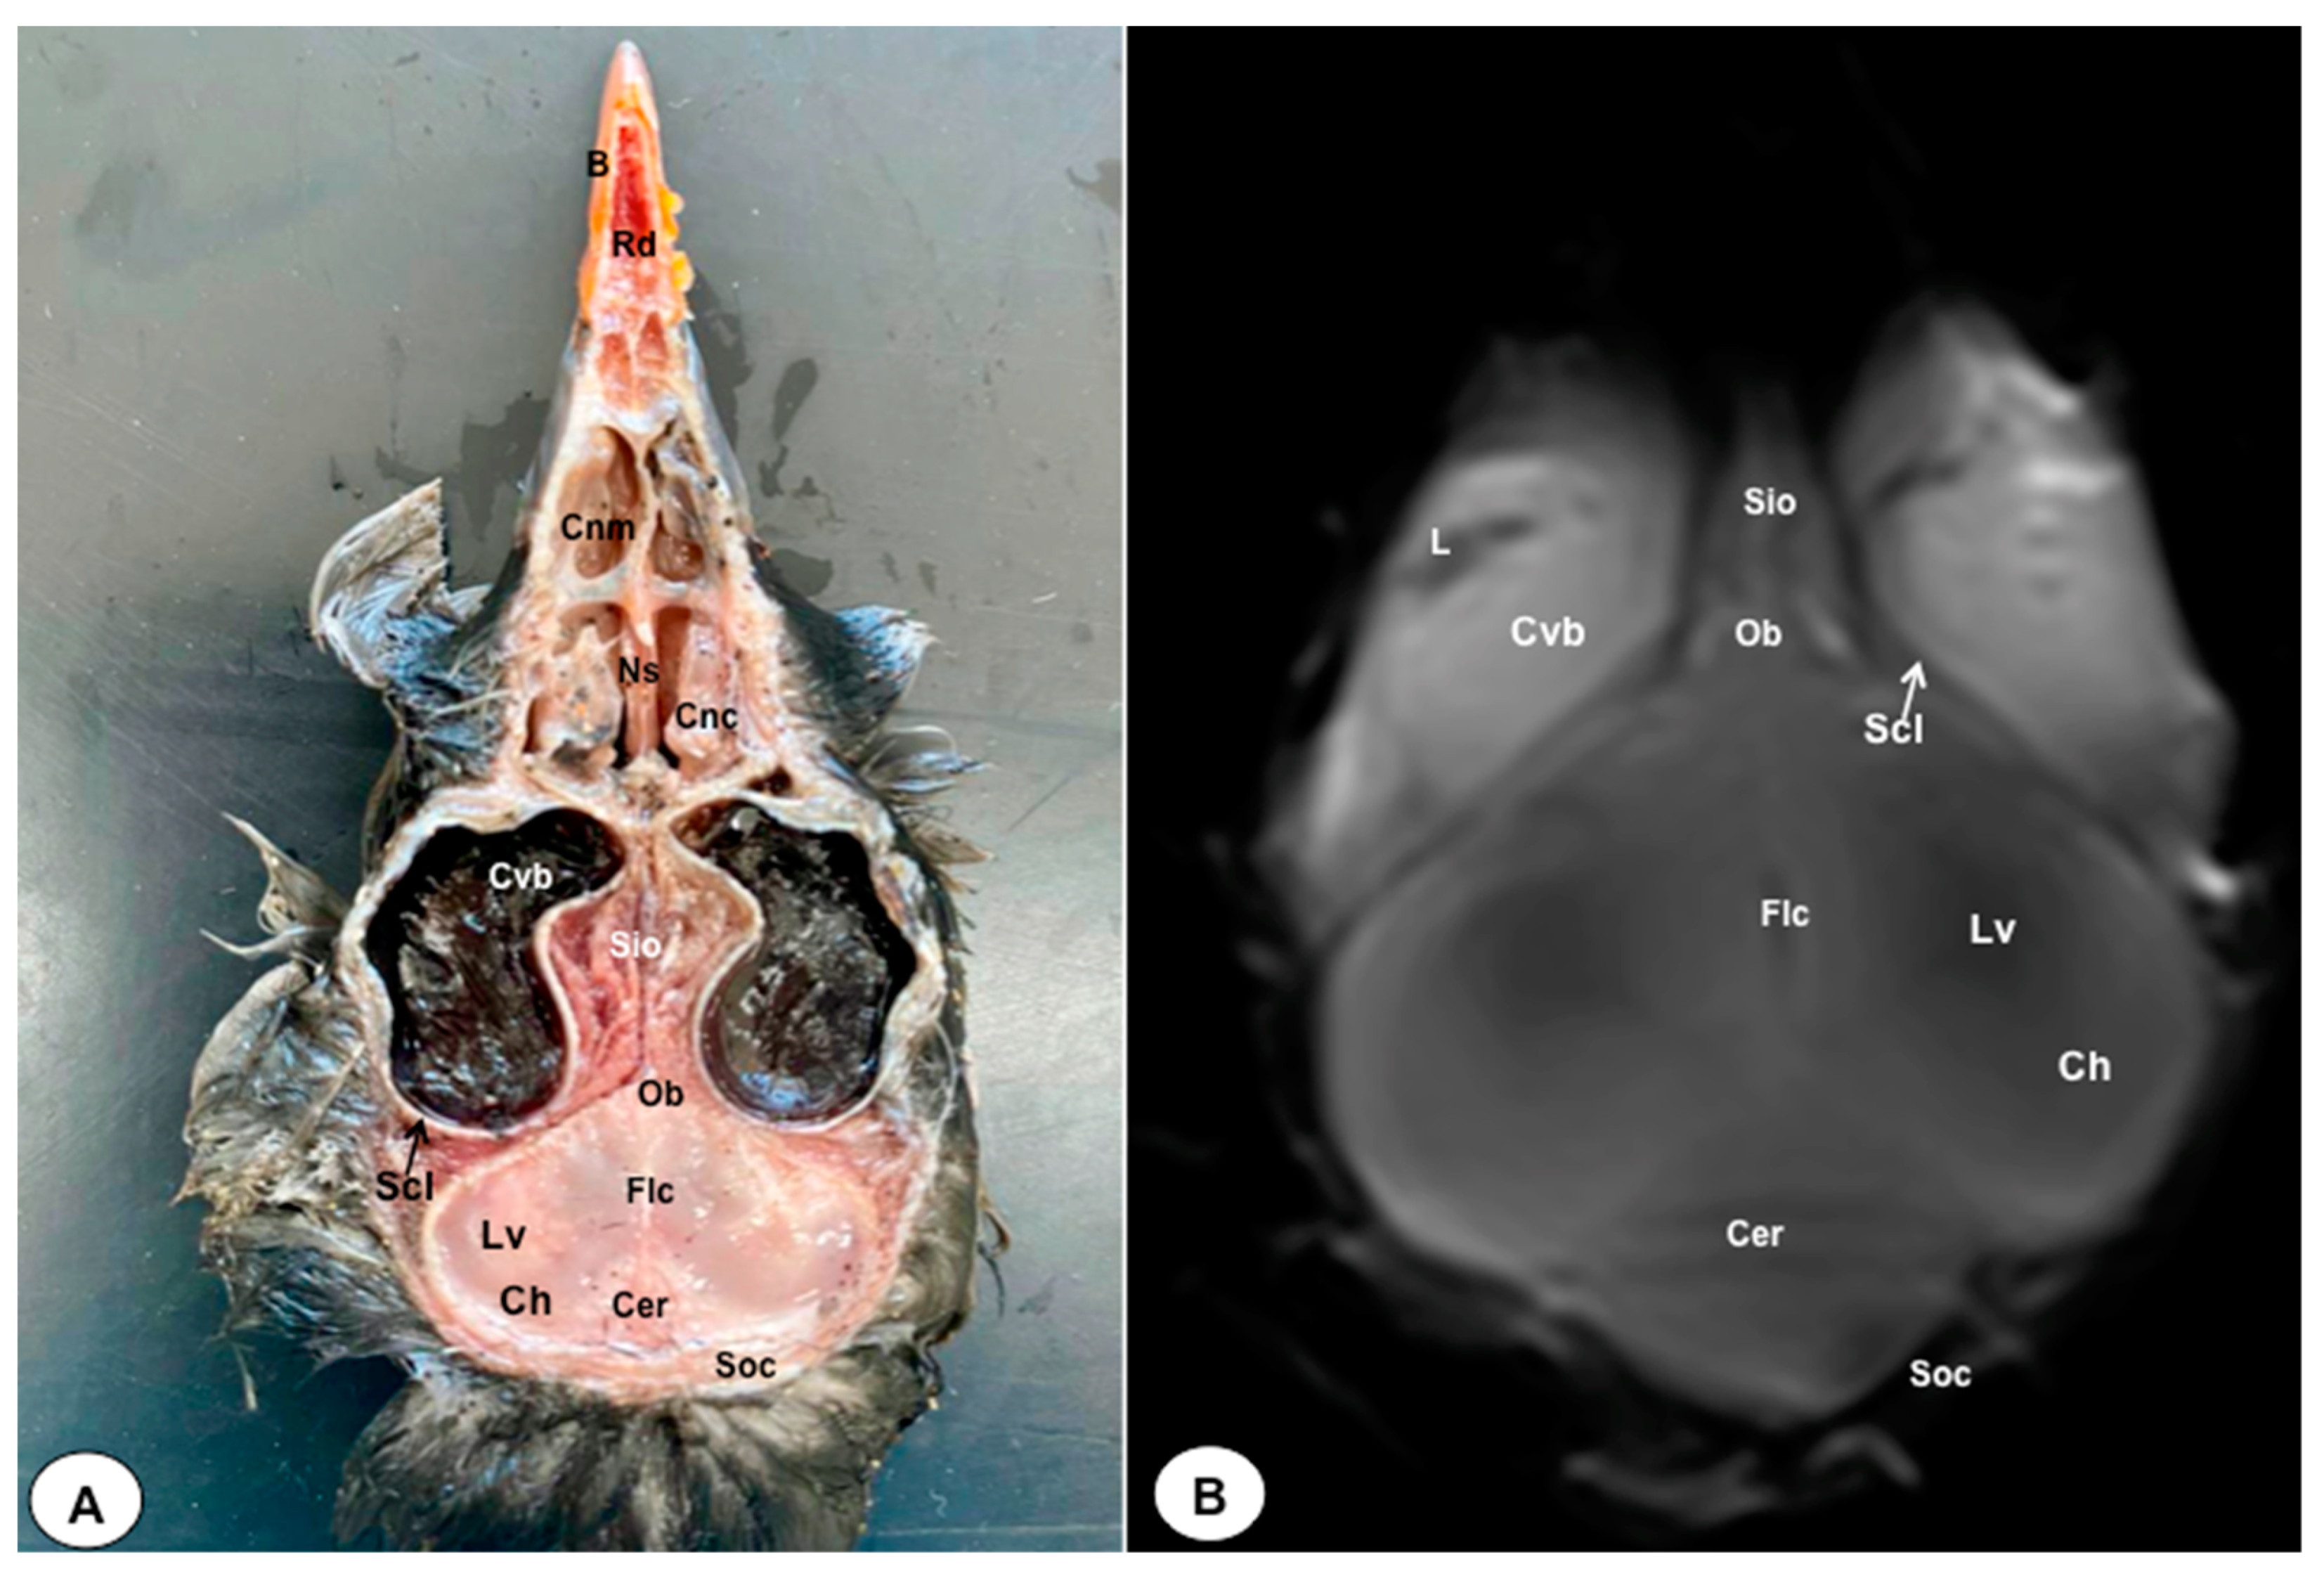

3.1. Anatomical Sections

3.2. Magnetic Resonance Imaging (MRI)